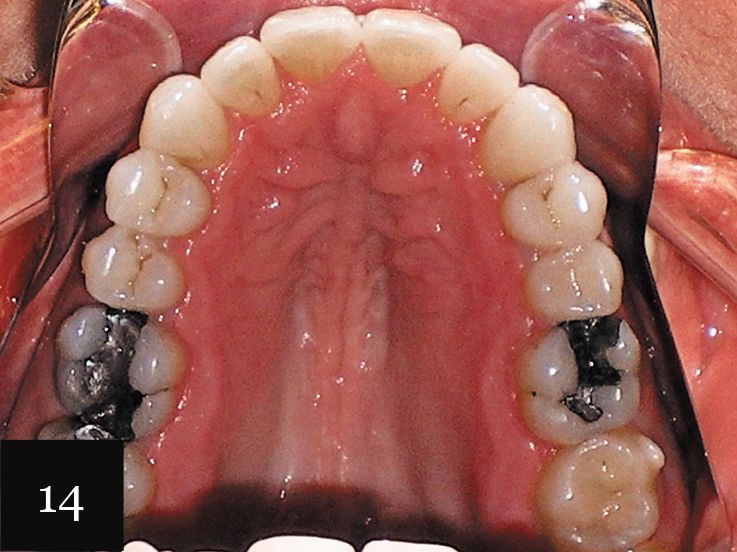

This treatment was performed on a male patient in his early 40s (Fig. 9). The patient had an omega-shaped upper arch, as seen in Fig. 10.

An impression was taken that successfully captured the complex crowding and narrow omega arch (Fig. 11), and the patient was treated with 28 aligners over 14 months. This case also illustrates use of the clear aligners as whitening trays, with the final result showing a smile that is not only straight, but also much brighter (Figs. 12-14).